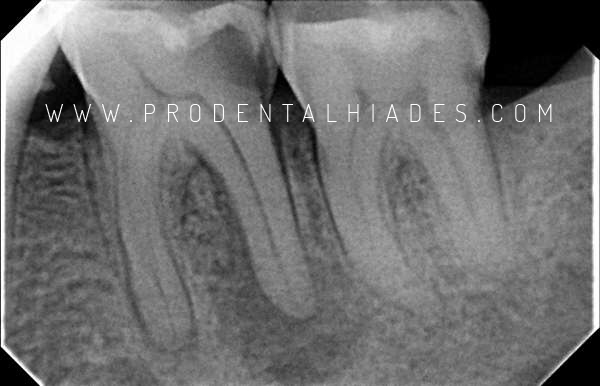

La Endodoncia consiste en limpiar y desinfectar bien todos los conductos del interior del diente que han sido contaminados por bacterias que proceden normalmente de una caries dental que ha avanzado hasta llegar a la capa más interna del diente “la pulpa dental“. Cuando ésto sucede, la pulpa dental reacciona ante dichas bacterias con inflamación desencadenando un proceso irreversible. El resultado es que el nervio dental y los pocos vasos que lo acompañan se necrosan quedando el interior del diente lleno de bacterias.

Todo este proceso puede causar mucho dolor, molestar ligeramente o incluso no sentir ninguna molestia. Al realizar la endodoncia limpiamos y desinfectamos todos los conductos del interior del diente hasta llegar a la punta de la raíz. sellando posteriormente este espacio herméticamente. De este modo eliminamos ese rincón donde las bacterias podrían reproducirse consiguiendo la curación del diente.

- Radiovisiografía: Permite realizar radiografías instantáneas de diagnóstico control del proceso del tratamiento con muy poca radiacción.